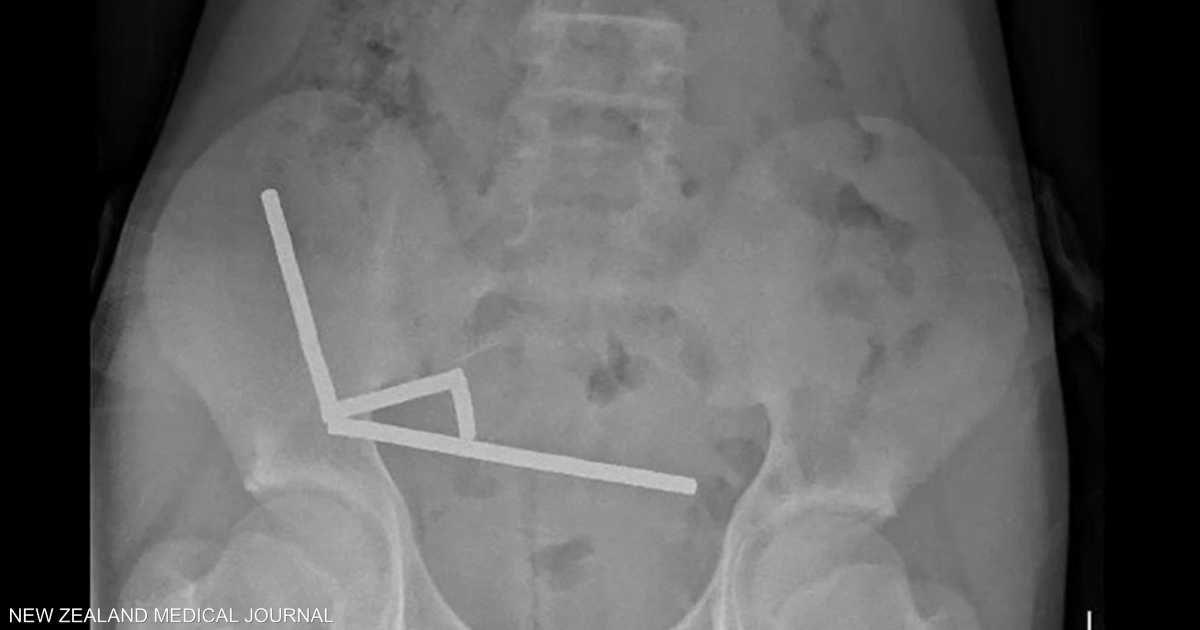

وأظهرت الأشعة أن المغناطيسات تكتلت معا في 4 خطوط مستقيمة داخل أمعاء المراهق، و"يبدو أنها كانت في أجزاء منفصلة من الأمعاء ملتصقة ببعضها البعض بسبب القوى المغناطيسية"، وفق الأطباء.

وأكد الأطباء أن ضغط المغناطيس تسبب في موت أنسجة في أجزاء من الأمعاء الدقيقة والغليظة.